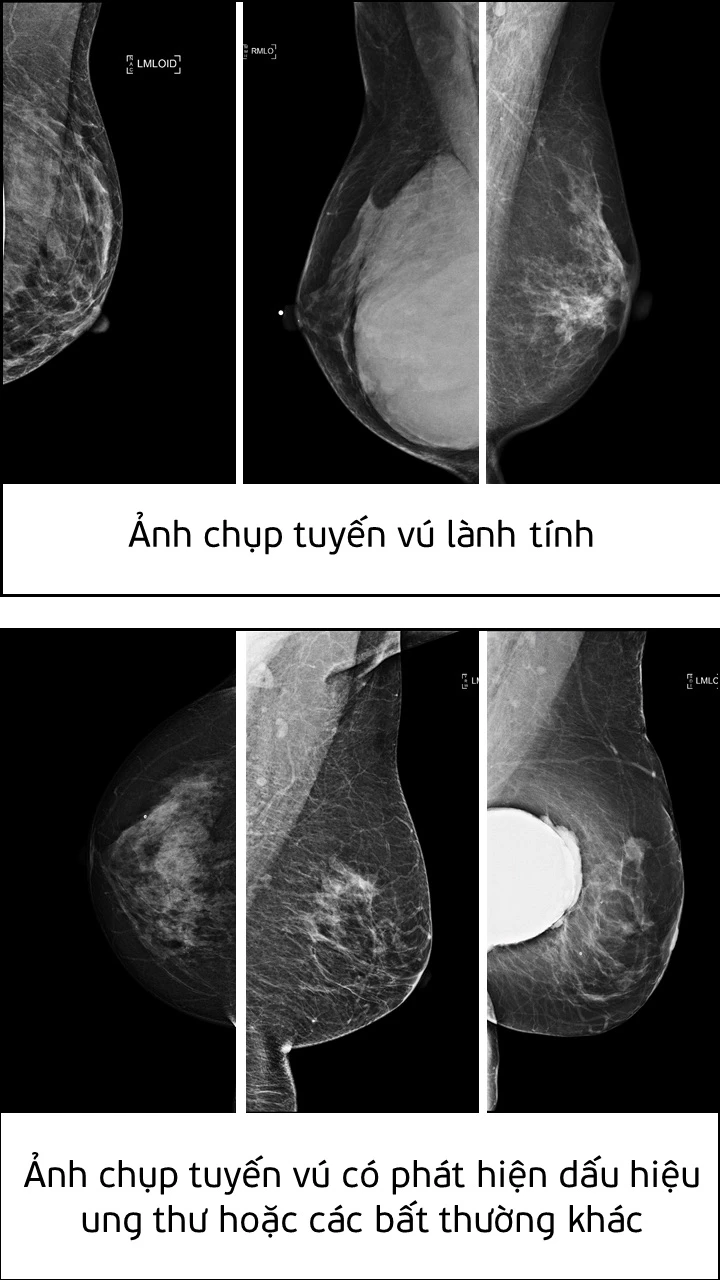

Giải pháp AI do Nguyễn Hồng Đăng phát triển có thể tự động nhận diện các dấu hiệu bệnh ung thư vú từ một vùng rất nhỏ trong nhũ ảnh. Giải pháp này có thể tích hợp vào hệ thống hỗ trợ phân tích (Computer-aided diagnosis - CADx systems) nhằm cải thiện tính chính xác trong việc chẩn đoán và khám chữa bệnh.

Theo đánh giá của Ban giám khảo, giải pháp của Nguyễn Hồng Đăng đã giải quyết được tình trạng mất cân bằng dữ liệu trong huấn luyện mô hình AI. Trong tệp dữ liệu mà cuộc thi đưa ra, tỷ lệ mẫu ung thư ác tính được gán nhãn chỉ chiếm khoảng 2% tổng số lượng mẫu, trong khi số lượng mẫu còn lại được gán nhãn lành tính hoặc bình thường chiếm 98%. Tình trạng mất cân bằng dữ liệu này có thể khiến cho trí tuệ nhân tạo dự đoán sai.